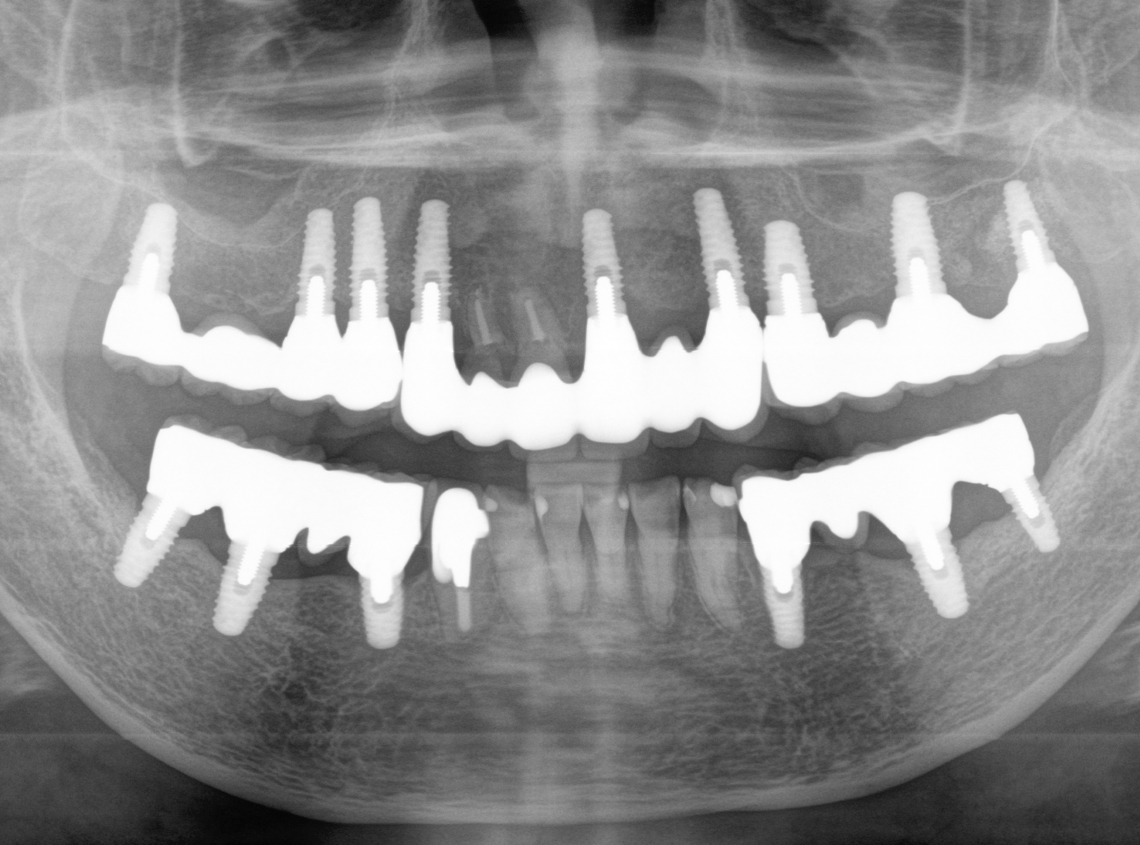

6.術後17年経過(2025年)

2025年4月10日撮影

インプラント埋入部の骨レベルは埋入時と変わらず、患者様ご自身のメンテナンスも良好で、経過は非常に良く、満足されています。